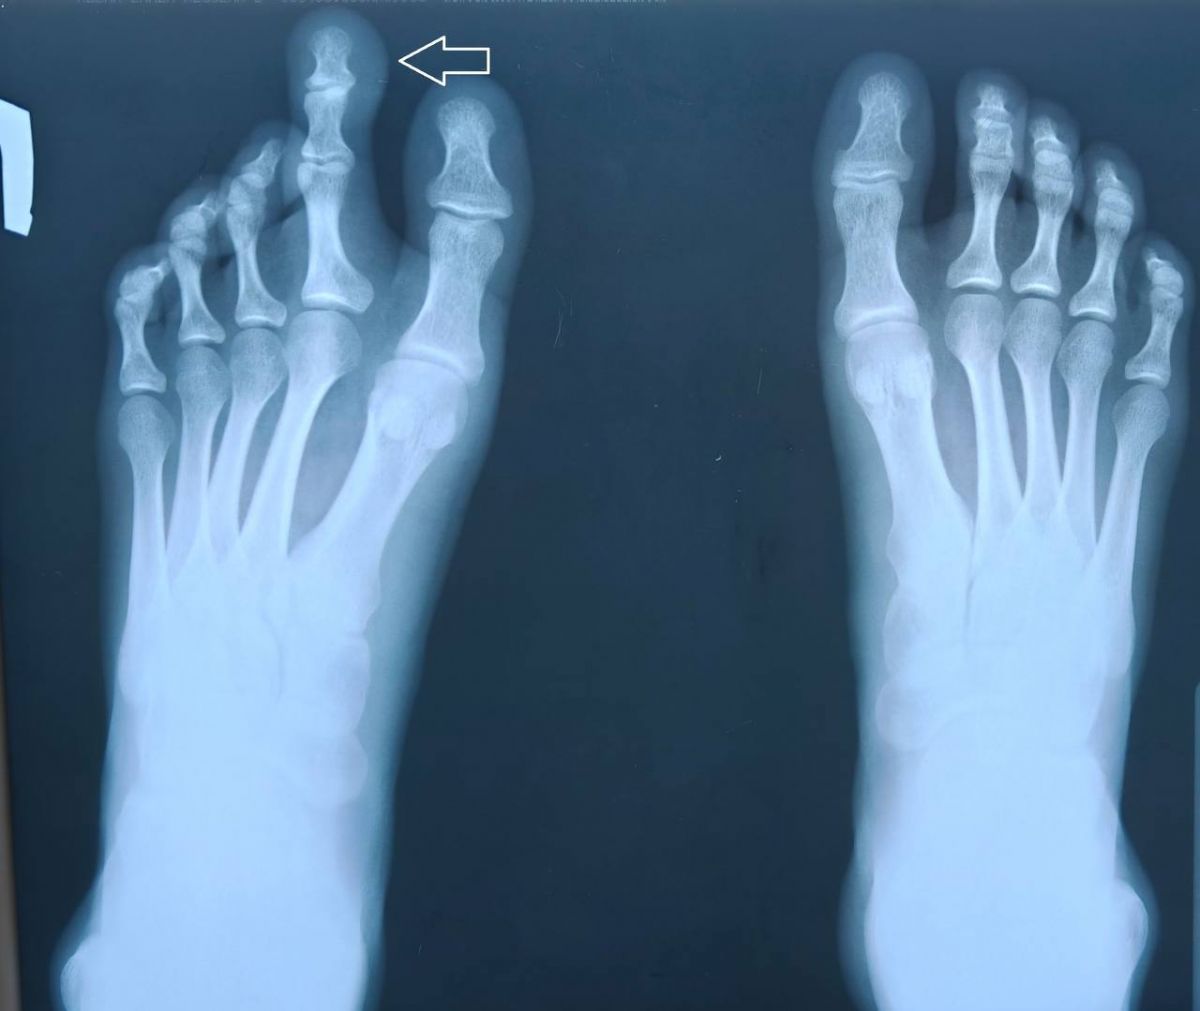

В Областном центре спецмедпомощи Пиганово рассказали о проведённой операции пациентке с парциальным гигантизмом — редкой врождённой аномалией, при которой чрезмерно увеличиваются отдельные части тела, чаще всего пальцы рук или ног.

На консультацию к специалистам центра обратилась 17-летняя девушка с сильно увеличенным вторым пальцем левой стопы. Она жаловалась на выраженный косметический дефект и сложности при подборе обуви. Травматолог-ортопед принял решение о проведении операции для коррекции аномалии.

Операцию выполнили врачи отделения травматологии и ортопедии №1 — Г. М. Чочиев и А. М. Рубцов, при участии операционной сестры А. Е. За харовой. Обезболивание обеспечивали врач-анестезиолог А. Г. Егоров и сестра-анестезист М. Г. Щаренкова. Во время операции провели реконструкцию второго пальца стопы: укорачивающую остеотомию с фиксацией костных фрагментов спицей и удалили избыточные мягкие ткани.

В результате был сформирован функционально и косметически полноценный палец. Пациентка поблагодарила команду специалистов.